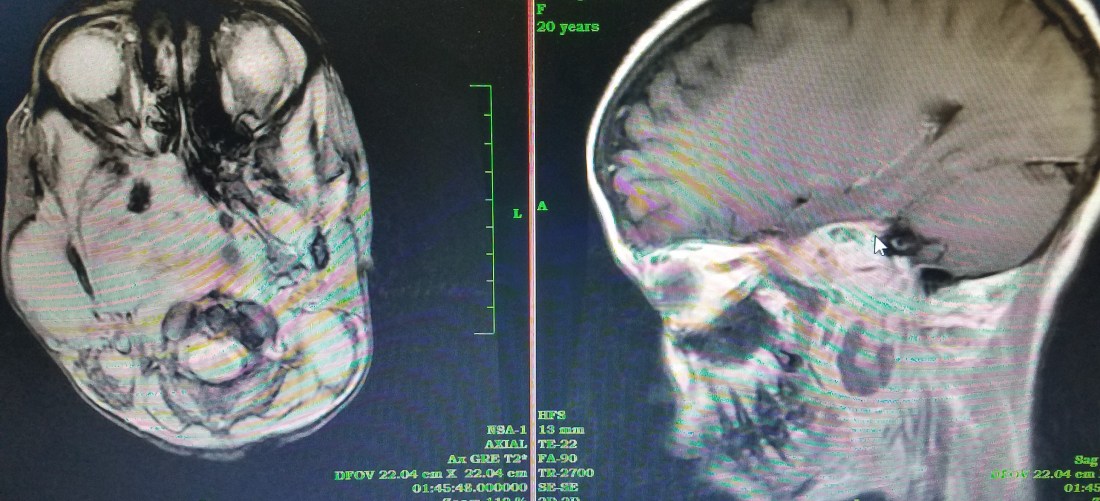

Just then, and I’m not exaggerating timing, one of the docs from the Oral-maxillary team comes in asking me to see a patient with him. He brings in a 20 year old girl with a proptotic right eye but covered by lid ptosis, a right parotid mass and a large left neck mass. He pulls up an MRI showing a large right parapharyngeal mass extending through the skull base into the intracranial space, obliterating the cone of the right orbit on its way. Without knowing for sure what this could be, I decided to take an excisional biopsy from the neck and the parapharyngeal mass through the soft palate and the nasopharynx. We will schedule this soon. Whatever this is, it looks aggressive and is in a bad space. I’m not sure what to predict for this young girl.